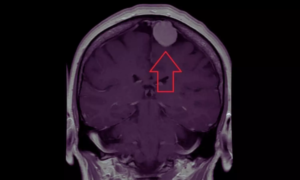

Depot Medroxyprogesterone Acetate Use Linked to Higher Meningioma Risk in Women: JAMA

Researchers have found in a new study that women using depot…